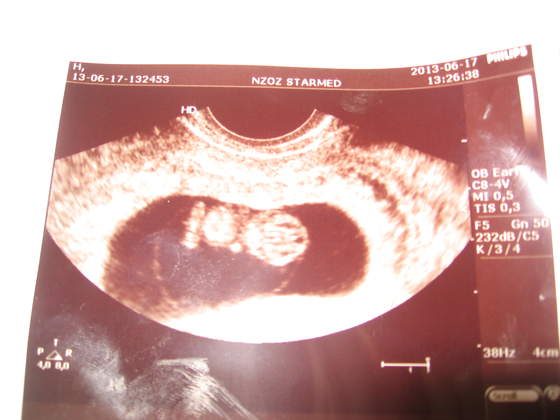

hej dziewczynki, dobre wiesci przynosze, dzidziunia rozwija sie prawidlowo, ma juz raczki, nozki, głowke, i mocno bijace serduszko :-):-):-):-):-) Picture 004.jpg

sylka11, piekny maluszek! :)